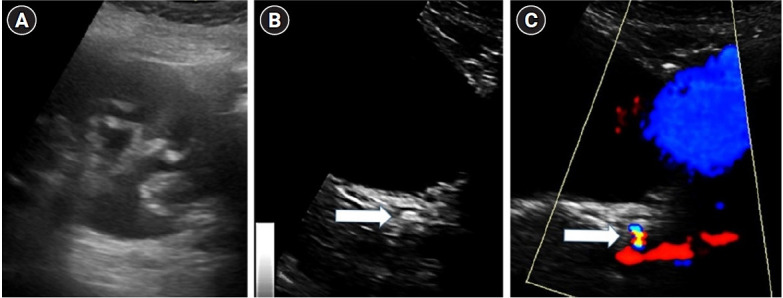

Symptomatic urolithiasis is a common cause of emergency department visits, with noncontrast computed tomography considered the imaging gold standard. According to the current guidelines, point-of-care ultrasound (POCUS) is limited to evaluating hydronephrosis as a secondary sign of acute ureteral stones. However, the use of POCUS to detect ureteral stones may lead to decreased radiation to the patient and a more rapid diagnosis. This case series describes 10 patients with suspected symptomatic urolithiasis who were diagnosed accurately by emergency physicians using POCUS to detect obstructive ureteral stones. In three of the cases, POCUS significantly changed the patient's management. This article also describes the proper techniques for the emergency physician to learn to master POCUS for ureteral stone detection.